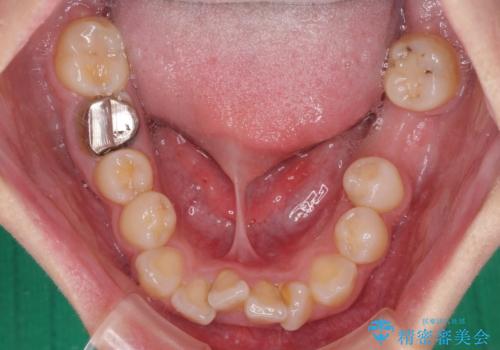

- 放置した虫歯や抜いたままの奥歯、前歯のデコボコを気にして来院された患者様です。

口元の突出感は少なく、下顎の叢生は軽微なものであったので、叢生の強い上顎左右の小臼歯を1本ずつ抜歯し、ワイヤー装置にて矯正治療を行うこととしました。

矯正治療を行う前に、根管治療の必要な上顎前歯と下顎大臼歯の根管治療を行い、矯正治療の途中で下顎の欠損部にインプラント埋入することとし、矯正治療後に補綴治療を行うこととしました。